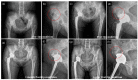

In orthopedics, a number of synthetic bone substitutes are being used for the repair and regeneration of damaged or diseased bone. The nature of the bone substitutes determines the clinical outcome and its application for a range of orthopedic clinical conditions. In this study, we aimed to demonstrate the possible applications of multichannel granular bone substitutes in different types of orthopedic clinical conditions, including bone tumor, fracture, and bone defect with arthroplasty. A clinical investigation on a single patient for every specific type of disease was performed, and patient outcome was evaluated by physical and radiographic observation. Brief physical characterization of the granular bone substitute and in vivo animal model investigation were presented for a comprehensive understanding of the physical characteristics of the granules and of the performance of the bone substitute in a physiological environment, respectively. In all cases, the bone substitute stabilized the bone defect without any complications, and the defect regenerated slowly during the postoperative period. Gradual filling of the defect with the newly regenerated bone was confirmed by radiographic findings, and no adverse effects, such as osteolysis, graft dispersion, and non-union, were observed. Homogeneous bone formation was observed throughout the defect area, showing a three-dimensional bone regeneration. High-strength multichannel granules could be employed as versatile bone substitutes for the treatment of a wide range of orthopedic conditions.